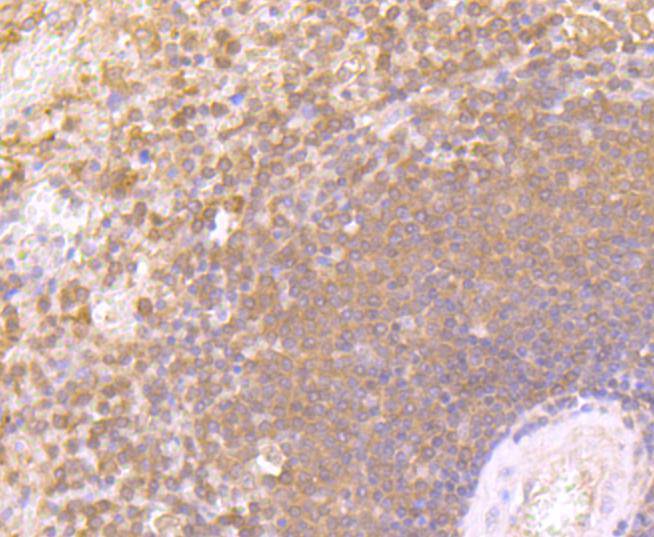

Immunohistochemical analysis of paraffin-embedded human tonsil tissue using anti-Interferon gamma antibody. Counter stained with hematoxylin.

,

Immunohistochemical analysis of paraffin-embedded human spleen tissue using anti-Interferon gamma antibody. Counter stained with hematoxylin.

Immunohistochemical analysis of paraffin-embedded mouse spleen tissue using anti-Interferon gamma antibody. Counter stained with hematoxylin.